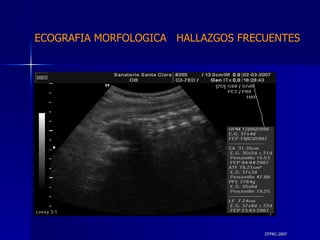

DTFRC-2007 ECOGRAFIA MORFOLOGICA  HALLAZGOS FRECUENTES   MATERIAL Y METODO ES UN ESTUDIO DESCRIPTIVO, RETROSPECTIVO  DE ESTUDIO ECOGRA FICOS REALIZADOS ENTRE MARZO 07 A MARZO 08 EQUIPO DE ALTA RESOLUCION   VOLUSON 730 PRO  MEDISON SA 8000 live MEDISON SA 8000SE CRITERIO DE INCLUSION:   POBLACION GENERAL    GESTACIONES  20 a 24 SEMANAS   UNIVERSO  N 211

DTFRC-2007 ECOGRAFIA MORFOLOGICA  HALLAZGOS FRECUENTES   Sistema Nervioso Central  8  Cardiovascular  0 Genitourinario  6 Musculos Esqueleticos  2 Gastrointestinales  2  Otros  12  Total  30   NUMEROS DE ANOMALIAS POR SISTEMA n N  211